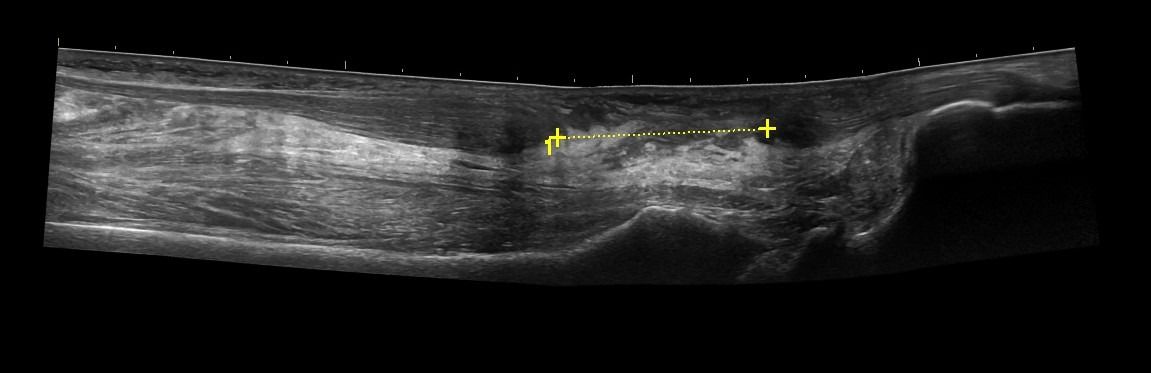

Foot Tendons

Foot Ultrasound allows the diagnosis of tendonitis, tenosynovitis, and rupture in the following tendons:

- Achilles Tendon

- Peroneal Tendons

- Flexor Tendons

- Extensor Tendons